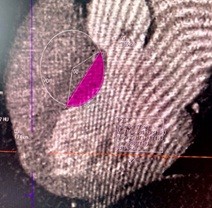

In the process of studying pathology on a computed tomography (CT), we obtain images (scans). Using the CT software, we can determine the radius of the hypertrophied part of the IVST (Fig. 6), and we can also draw and measure the line of the proposed excised part.

Figure 6. Computed tomography image: Determination of the radius of hypertrophied part for excision

• find the area of the unsubtracted part (circle segment) shaded in pink at the condition that the radius (R) of the circle with center at point O and the length of the cut-off segment AB (Fig. 6) are known;

For the above example, using the CT scanner software, we have: